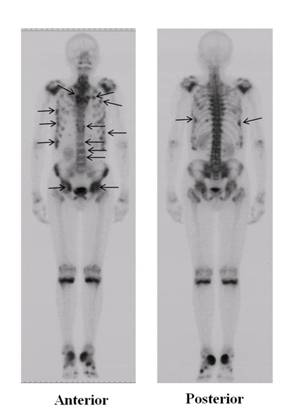

USA). Bone scintigraphy with 99mTc-methylene

diphosphonate revealed abnormal tracer uptake in multiple bones

including the spine, ribs, pelvis and femurs, suggesting

clinical fractures (Fig. 1). Laboratory findings showed that the

Figure 1

Bone scintigraphy of the patient

Bone

scintigraphy with 99mTc-methylene diphosphonate

revealed abnormal tracer uptake in multiple bones including the

spine, ribs, pelvis and femurs (arrows).